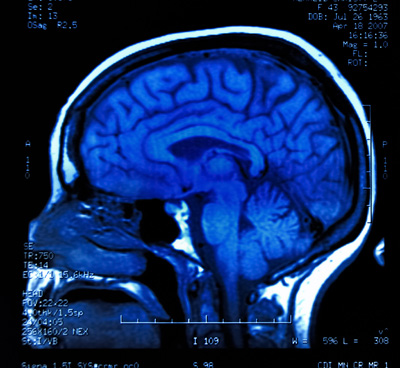

Представьте себе, что каждая игровая сессия – это своего рода тренировка для мозга, где мы постоянно адаптируемся к меняющимся условиям, учимся новым правилам и стратегиям. Это не просто метафора; исследования активности мозга геймеров с помощью ЭЭГ и фМРТ показывают реальные изменения в объеме серого вещества, плотности нейронных связей и эффективности работы различных зон мозга. Например, мы видим усиление активности в префронтальной коре, отвечающей за планирование и принятие решений, а также в гиппокампе, играющем ключевую роль в формировании памяти и пространственной ориентации. Эти изменения не ограничиваются только игровым процессом, они переносятся и в реальную жизнь, улучшая наши способности к обучению и адаптации в самых разных сферах.

Исследования с использованием функциональной магнитно-резонансной томографии (фМРТ) и электроэнцефалографии (ЭЭГ) показывают, что мозг геймеров демонстрирует уникальные паттерны активности. Мы наблюдаем активацию обширных нейронных сетей, отвечающих за внимание, память, принятие решений и эмоциональную регуляцию. Эти данные помогают нам не только подтвердить когнитивные преимущества игр, но и лучше понять механизмы, лежащие в основе как пользы, так и потенциальных рисков, связанных с геймингом.

Когда мы играем, наш мозг работает на полную мощность. ЭЭГ, измеряющая электрическую активность мозга, показывает изменения в мозговых волнах, указывающие на повышенную концентрацию и вовлеченность. ФМРТ, в свою очередь, позволяет нам увидеть, какие области мозга потребляют больше кислорода, то есть активно работают. И мы видим, что у геймеров активируются такие зоны, как дорсолатеральная префронтальная кора (связанная с рабочей памятью и исполнительными функциями), теменная кора (пространственное внимание) и даже зрительная кора, которая, как мы знаем, становится более эффективной в обработке визуальной информации.

Долгосрочные исследования показывают, что длительный гейминг может влиять на структуру мозга, увеличивая объем серого вещества в областях, связанных с навигацией, стратегическим планированием и формированием памяти. Например, у игроков в стратегические игры часто наблюдается увеличение объема в гиппокампе и префронтальной коре. Эти структурные изменения являются прямым доказательством нейропластичности в действии – наш мозг буквально перестраивается, чтобы лучше справляться с задачами, которые мы ему регулярно предлагаем.